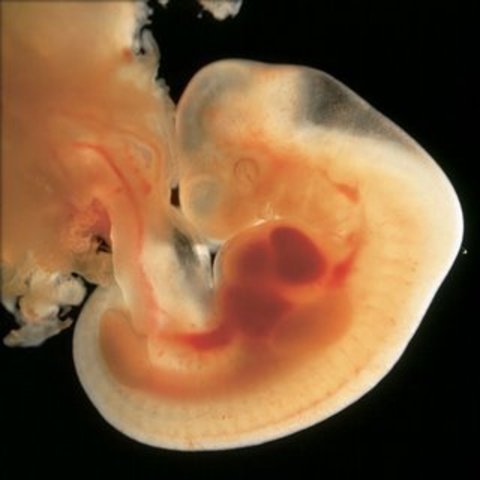

Once it's implanted, the blastocyst is now an embryo. This is the beginning of the embryonic period as well. Also, the placenta begins to form at this time. The placenta is important because it provides the embryo with nutrients, gets rid of waste, and exchanges respiratory gases.

• Organs Begin to Develop

Organs Begin to Develop

Brain, spinal chord, heart, muscles, back bone, ribs, and digestive track start to form at this early stage in the embryonic period.

• Ectoderm, Mesoderm, and Endoderm

Ectoderm, Mesoderm, and Endoderm

The Ectoderm, Mesoderm, and Endoderm are developing. The ectoderm will give rise to the outermost layer of skin, central and peripheral nervous systems, eyes, inner ear, and many connective tissue. The mesoderm is the middle layer that will also serve as the foundation for your baby's bones, muscles, kidneys and much of the reproductive system. The endoderm will become a simple tube lined with mucous membranes. The lungs, intestines and bladder will develop here.